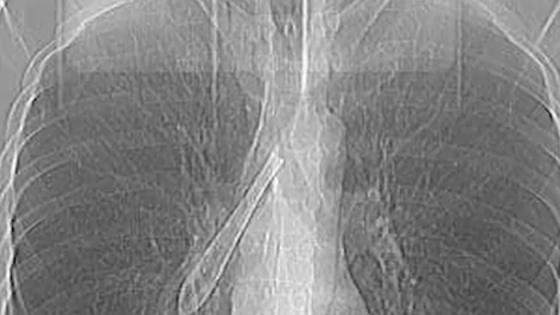

В Казани заключенный проглотил черенок от ложки и проходил с ним в легких больше года. Администрация колонии запрещала госпитализировать мужчину, поскольку он нарушил порядок, сообщает Telegram-канал Mash Iptash.

Около года назад работники ФСИН сообщили мужчине, что оставшийся срок он проведет в другом месте. Тогда россиянин отделил рукоятку от чашки и проглотил ее. Таким образом мужчина решил остановить процедуру своего перевода.

Поступок заключенного не обрадовал администрацию исправительного учреждения, и его не отпустили в больницу.

Оставшееся время наказания мужчина провел с инородным предметом, за год черенок буквально сросся с бронхами. После освобождения россиянин обратился в медицинское учреждение, и хирурги провели ему операцию без наркоза.